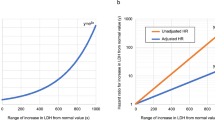

In the derivation cohort, correlation analysis showed that there were significantly positive associations between baseline CT severity score and inflammatory indexes (neutrophil count, lactic dehydrogenase, and C-reactive protein) on admission (Fig. 4a). Furthermore, for 134 patients who had available inflammatory indexes results on day 3 after admission in the derivation cohort, baseline CT severity score was not only positively associated with inflammatory indexes (white blood cell count, neutrophil count, lactic dehydrogenase, and C-reactive protein), but also negatively associated with lymphocyte count on day 3 after admission (Fig. 4b), which indicated the potential of CT severity score for early predicting lymphopenia.